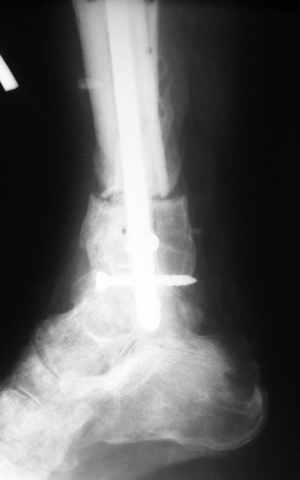

|  |  |  |  status localis на 14.11.08 (В ране визуализируется сухожилие.) | Больной А, 40 лет, находится в клинике с 15.10.08 с диагнозом: Сочетанная травма. Ушиб головного мозга лёгкой степени тяжести. Компрессионные переломы тел 12 грудного и 5 поясничного позвонков без неврологических осложнений. Закрытый внутрисуставной многооскольчатый перелом дистальных метаэпифизов обеих костей правой голени со смещением. Открытый внутрисуставной многооскольчатый перелом дистальных метаэпифизов обеих костей левой голени со смещением (см. Р-граммы). Хронический алкоголизм. Доставлен СМП после падения с 5-го этажа (не суицид). При поступлении состояние тяжелое. Глубокое оглушение. Дыхание самостоятельное, адекватное. Гемодинамика стабильная. По внутренней поверхности левой голени, в нижней трети, рвано-ушибленная рана 10-6 см, из раны выстоит проксимальный отломок большеберцовой кости, рана обильно загрязнена землёй. Интенсивная терапия в условиях реанимационного отделения, вытяжение за правую пяточную кость, параартериальная блокада обеих нижних конечностей, гипсовая лонгета на левую нижнюю конечность, ас-повязка на рану. Через 4 часа после поступления оперирован: после неоднократного промывания раны тёплой проточной водой с мылом, антисептиками, при ревизии определяется земля в канале проксимального отломка на глубину 3 см..., отсутствие надкостницы на концах дистального и проксимального отломков на 3 см. Удалено значительное количество мелких костных фрагментов, перемешанных с землёй, выполнена ПХО раны, резекция проксимального конца большеберцовой кости на 3,5 см, ЧКДО аппаратом Илизарова. Рана не ушивалась. В последующем перевязки раны с "Левомеколь", через 3 недели с момента травмы в ране определялись грануляции, нежизнеспособный конец дистального отломка. 10.11.08 ВХО раны, резекция дистального отломка на 3 см, перемонтаж аппарата наружной фиксации (см. Р-граммы). Отломки сближены на 2 см (остеотомию малоберцовой не делали). В настоящее время (5 сутки после операции) незначительное количество серозного отделяемого из раны, имеется дефект кости 4 см (см. Р-граммы). В последующем склоняемся к перемонтажу аппарата наружной фиксации, остеотомии малоберцовой кости в области повреждения, сближении отломков. По заживлению раны удлинение левой голени на 4 см. Однако, некоторыми высказывалось мнение о необходимости артродеза. Представляем рентгенограммы левой голени при поступлении, после повторного оперативного лечения и фото st.localis на 14.11.08. Будем очень благодарны за критику, комментарии, пожелания и мнения о дальнейшей тактике лечения.

Больному выполнена резекция малоберцовой кости, ВХО раны, сближение отломков. Резекция м\б через отдельный разрез. После ВХО компрессия в аппарате, края раны сближены наводящими швами (без натяжения).

В случае гладкого заживления раны, при условии положительного решения вопроса с металлом, планируем перемонтаж аппарата Илизарова, дополнительную резекцию дистального отломка, выведение полокости голеностопного сустава в правильное положение (см. боковую Р-грамму), одномоментно остеотомия большеберцовой кости. После восстановления длинны голени, по всей видимости, артродез голеностопного сустава.

Рентгенограммы прилагаются. Фото местного статуса выложу в ближайшее время.